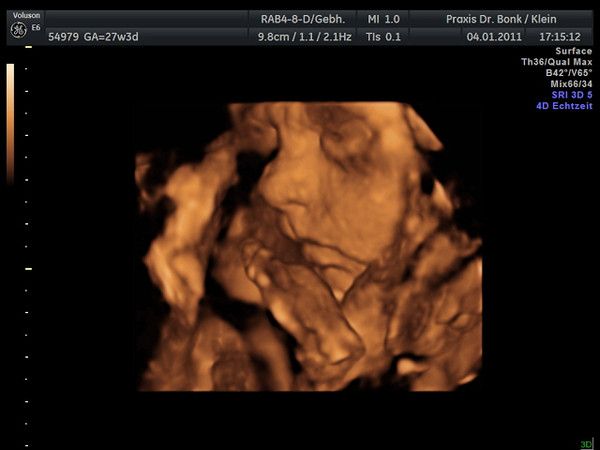

Tinchen´s Krümelchen 13. +1 (14. SSW)

13.10.2010

Krümel ist jetzt 8,7 cm groß. Das Herz hat ganz fleißig geschlagen. Und eine gratis Turnstunde gab es auch noch zu sehen.